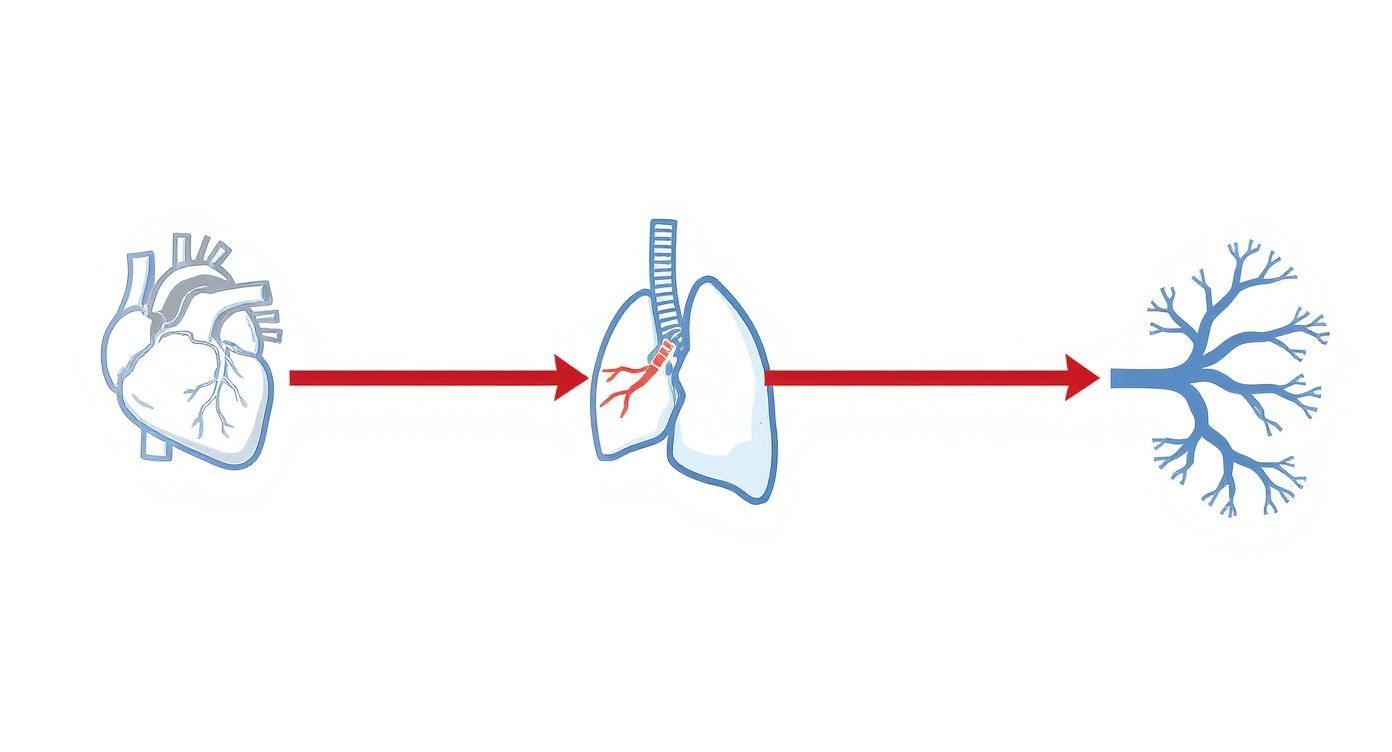

Die folgende Grafik zeigt dir den Weg des Blutes vom Herzen zur Lunge und zurück in einer ganz einfachen Darstellung.

Du siehst hier ganz klar, wie das sauerstoffarme (blaue) Blut von der rechten Herzhälfte zur Lunge gepumpt wird und als sauerstoffreiches (rotes) Blut zur linken Herzhälfte zurückkehrt.